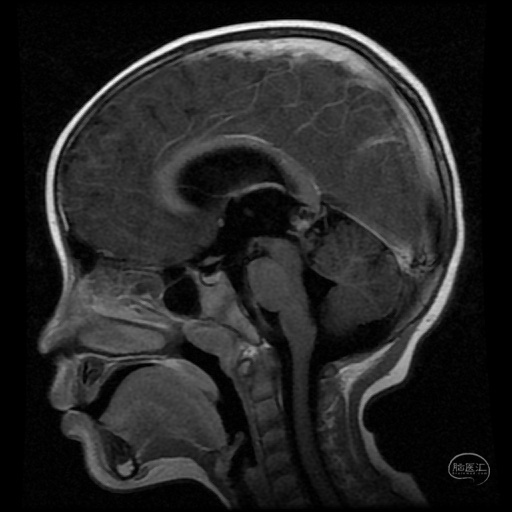

3岁男性患儿,间断头痛两个月入院,头部MR检查结果提示松果体区占位病变并梗阻性脑积水。

矢状位MR可见松果体区占位病变。